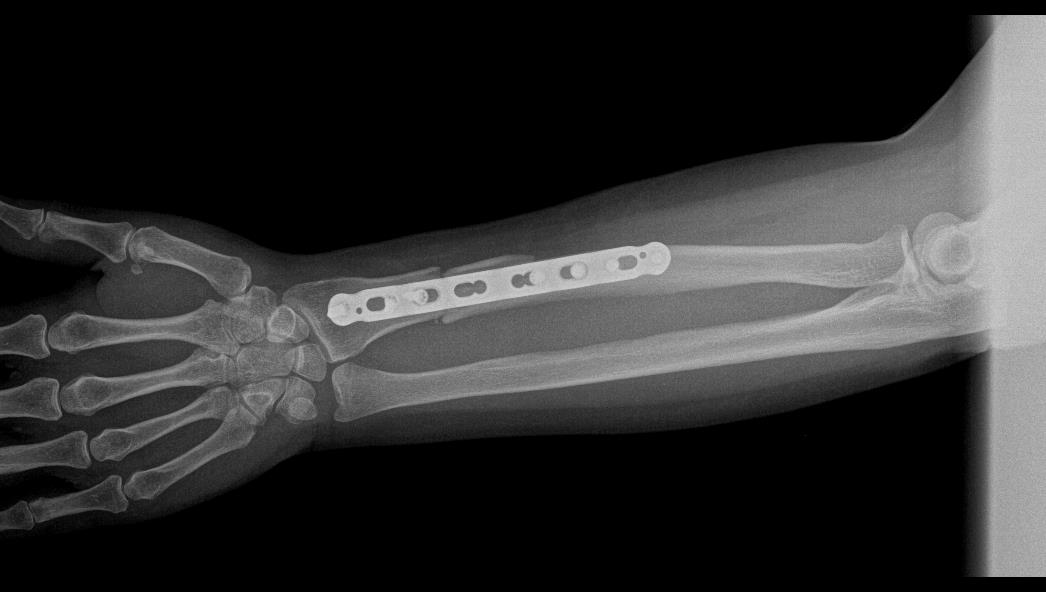

TRUE LOCK 3.5mm Ulna Radius Plate

TRUE LOCK 3.5mm Ulna Radius Plates are indicated for fractures of ulna, radius and fibula shaft.

Images Gallery